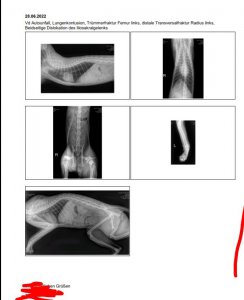

16.07.2022 Casi's Unfall… und nun auch noch Cosimo verletzt Beitrag #206 mennemaus Ehren-Mitglied Beiträge 24.139 Reaktionspunkte 17.737 Au wei, wenn man diese Fotos sieht, weiß man erst, wie schlimm die Verletzungen von Casi gewesen sind. Toll, dass die Ärzte es geschafft haben, die zerbröselten Knochen wieder zusammenzusetzen. Dein Casi hat richtig Glück gehabt, dass die Ärzte nicht amputiert haben, sondern dass sie die schwierige OP gewagt haben. Hoffentlich heilt das alles gut und hoffentlich bleiben keine Folgeschäden von dem Unfall übrig. Alles Gute für den kleinen Racker.

16.07.2022 Casi's Unfall… und nun auch noch Cosimo verletzt Beitrag #207 Fusselschreck Beiträge 1.755 Reaktionspunkte 981 Als ich das erste Röntgenbild am Tag des Unfalls sah, sah ich nur Splitter. Ich hatte es noch viel schlimmer in Erinnerung, wahrscheinlich auch durch den Schock. War ja alles so schlimm an dem Tag

Als ich das erste Röntgenbild am Tag des Unfalls sah, sah ich nur Splitter. Ich hatte es noch viel schlimmer in Erinnerung, wahrscheinlich auch durch den Schock. War ja alles so schlimm an dem Tag